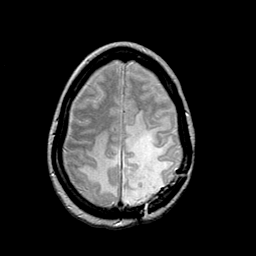

MR Study #2 -- Slice #40